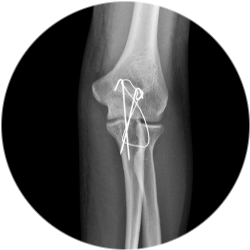

Ход остеосинтеза локтевого отростка:

Придание пациенту правильного положения на операционном столе.

Проведение общего наркоза.

Антисептическая обработка места манипуляции.

Разрез тканей в области локтевого отростка и создание визуального доступа к кости.

Сопоставление костных отломков, возвращение на место смещенных костей, восстановление целостности сосудов и нервов, удаление нежизнеспособных тканей.

Введение металлических спиц и их фиксация с помощью проволоки.

Вторичная обработка с использованием антисептика, наложение швов и стерильной повязки.

Перевод больного в палату стационара.